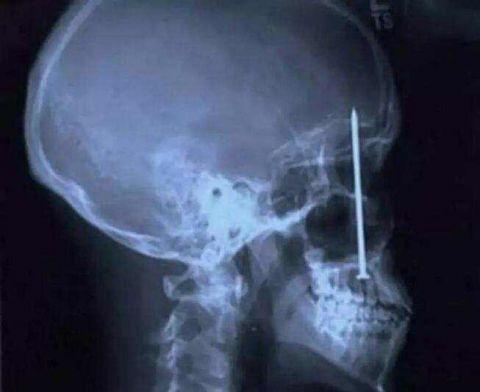

这个工人老说自己牙疼,检查后才发现这玩意儿